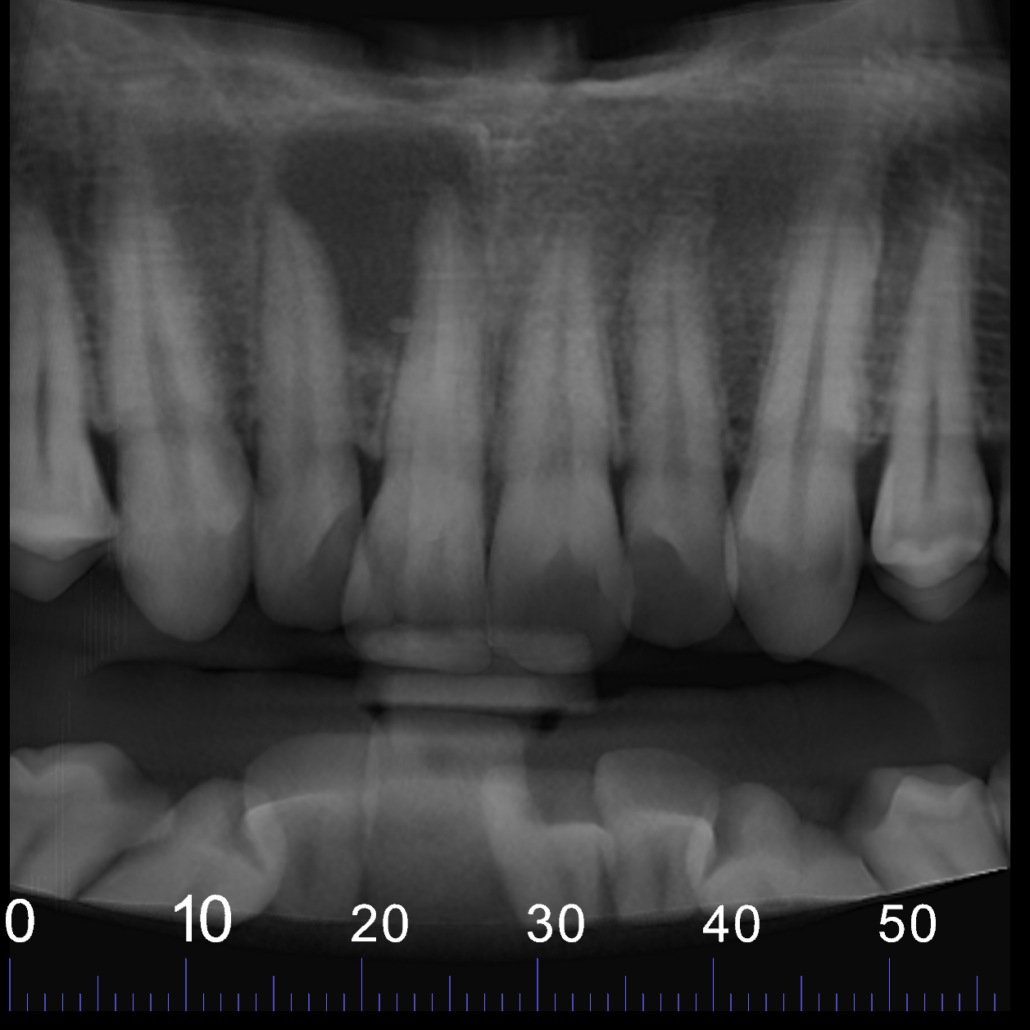

CBCT reconstructed panoramic image

Cropped panoramic, axial and cross section of alveolar ridge UR1 region. UR1 is root filled to the apex with a small amount of extruded filling material inside the lesion (arrow)